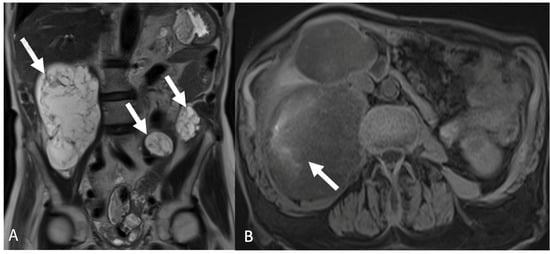

4. Imaging

5.3.1. Disseminated Peritoneal Leiomyomatosis

5.3.2. Peritoneal Carcinomatosis